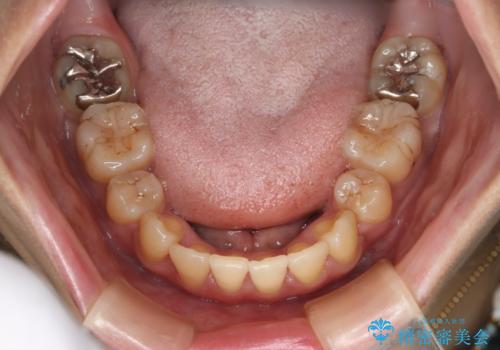

前歯を後ろに下げたい ワイヤー矯正(クリア装置)

- 2年

抜歯を行うことで前歯を後ろへ下げるスペースを獲得し、口元の突出感や歯のガタつきを改善していきました。